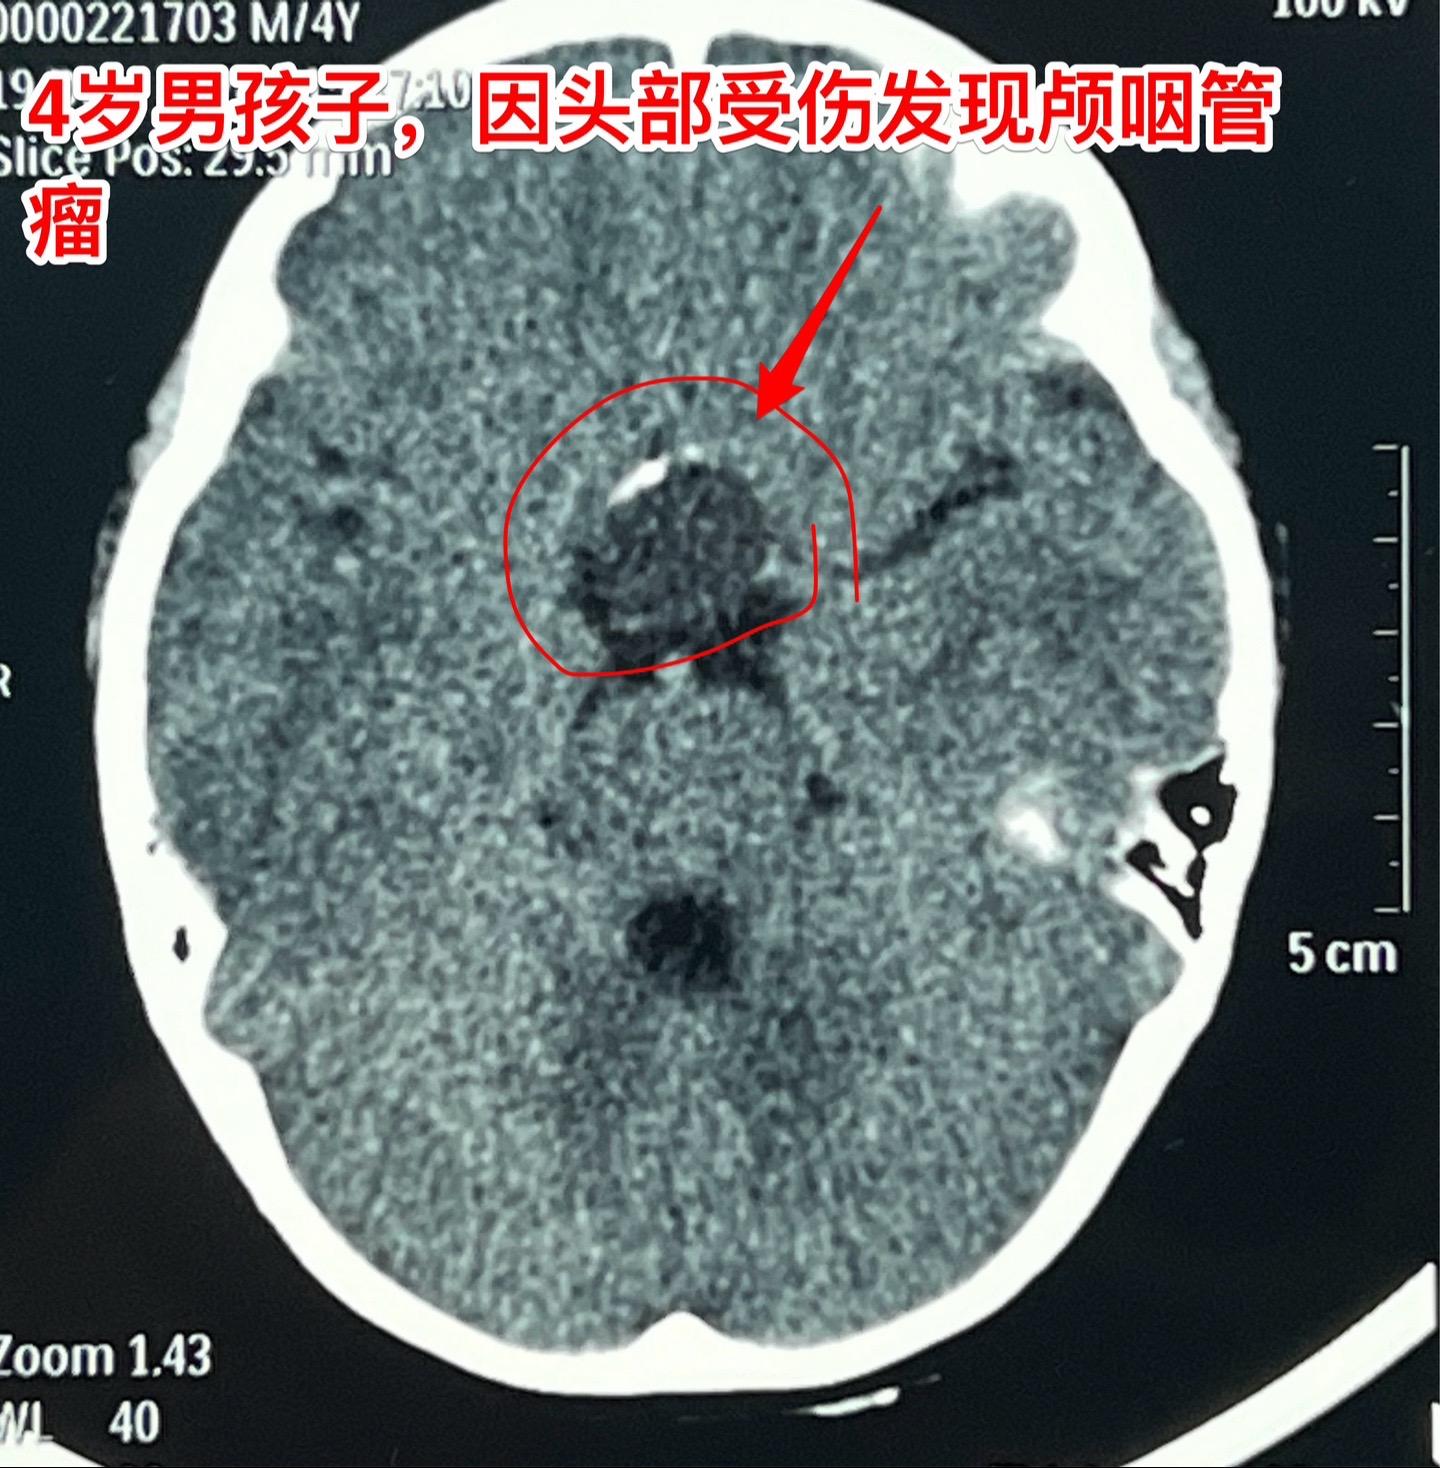

12月26日两个颅咽管瘤手术。第一个四岁男孩子,因为头部受伤,作CT发现颅咽管瘤。家长没有犹豫,选择尽快作手术。手术中将颅咽管瘤完全切除,垂体柄和垂体保留约50%。早作手术的好处就是肿瘤与周围结构粘连不紧密,易于分离,有助于完全切除肿瘤。 第二个病人是14岁男孩子,颅咽管瘤手术后6年,术后半年就发现了肿瘤复发,随后观察,多次复查磁共振显示肿瘤在长大。这个瘤也是在垂体窝内,和第一个病人一样,但是肿瘤与周围结构粘连紧密,切除的难度更大,也得到了完全切除。